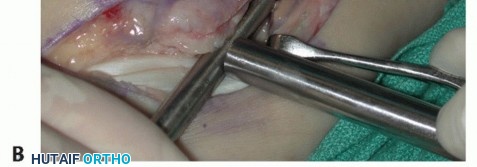

TECH FIG 1 • A. Intraoperative photograph of a left ankle (lateral approach) shows the peroneal tendons subluxing anteriorly (brevis is the gray arrowhead , longus is the white arrowhead , SPR is the black arrow). B. The peroneal tendons have been retracted anteriorly by the Penrose drain. Elevation of an anterior-based periosteal flap (outlined by dots) from the fibular groove has been completed. The black arrow shows the remnant of the SPR posteriorly. C. The tendons are relocated, after a groove-deepening procedure, into the recreated groove. The white dots outline the anteriorly based periosteal flap. It is then brought over to the posterior remnant of the SPR (black arrow). D. The flap is sutured to the remnant SPR with nonabsorbable sutures, completing the superior peroneal retinaculoplasty. |

| Make an incision in the peroneal sheath along the posterior border of the fibula. Retract the peroneal tendons anteriorly (TECH FIG 1B). | |||

| We routinely reinforce the SPR with a soft tissue periosteal flap elevated from the fibular groove from a posterior to anterior direction. | |||

| Raise the periosteal flap, measuring about 1.0 × 3.0 cm, sharply, from posterior to anterior. After the flap is | |||

| raised, a groove-deepening procedure may be performed when indicated. | |||

TECH FIG 1 • A. Intraoperative photograph of a left ankle (lateral approach) shows the peroneal tendons subluxing anteriorly (brevis is the gray arrowhead , longus is the white arrowhead , SPR is the black arrow). B. The peroneal tendons have been retracted anteriorly by the Penrose drain. Elevation of an anterior-based periosteal flap (outlined by dots) from the fibular groove has been completed. The black arrow shows the remnant of the SPR posteriorly. C. The tendons are relocated, after a groove-deepening procedure, into the recreated groove. The white dots outline the anteriorly based periosteal flap. It is then brought over to the posterior remnant of the SPR (black arrow). D. The flap is sutured to the remnant SPR with nonabsorbable sutures, completing the superior peroneal retinaculoplasty.